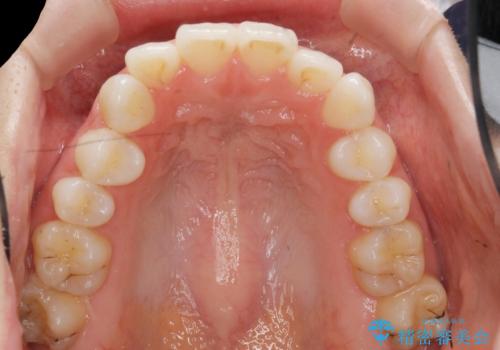

歯を抜かずに後方移動で達成する、前突感の改善

- 前歯が出っ歯のように見えることの改善を求めて来院されました。

当初、セラミックによる治療をご希望されていましたが、相談の結果矯正治療を選択されることとなりました。

通常口元の突出感の改善を行うには小臼歯の4本抜歯が検討されますが、歯のガタ付きが下顎前歯に限定していることから

下顎前歯を1本だけ抜去を行い、上顎の歯は可及的にマイクロインプラントを用いた後方移動を行い口元の印象の改善を計画することとなりました。

マイクロインプラントを用いてしっかりと後方移動を行ったことで前歯の角度は改善され、口元もすっきりと仕上げることができました。